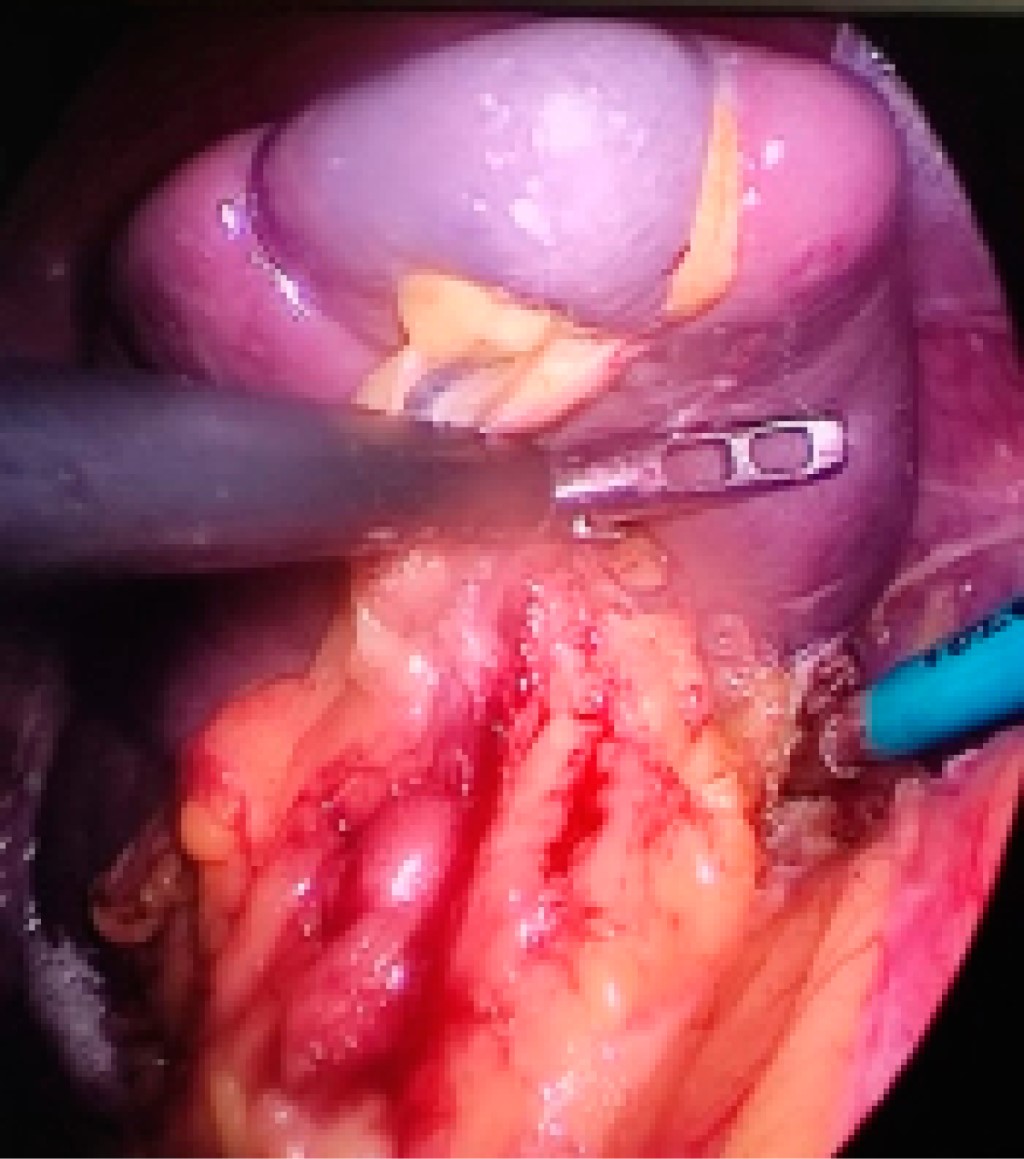

Elective laparoscopic splenectomy at the National Northeastern Medical Center. Case series report

Aguirre-Flores K, Mazariegos-Gutiérrez UE, Gómez-Arenas SR, Nacud-Bezies YA

Introduction: since the early 1990's, laparoscopic splenectomy has been performed with excellent results in multiple centers. This study reports the experience with this procedure at the National Northeastern Medical Center. Material and methods: retrospective and observational study of patients surgically treated with laparoscopic splenectomy in the period from March 2018 to May 2022, analyzing demographic, diagnostic, preoperative, transoperative and postoperative variables. Results: the database of 27 patients was reviewed, of whom 85.18% were women, and the average age was 36.4 years. The main diagnosis was immune thrombocytopenic purpura in 73.30%. The average operative time was 126.9 minutes. The average length of hospital stay after surgery was 25.3 hours. Only one patient presented surgical site infection. The percentage of patients with complete response to treatment was 85.18% and 14.82% presented a partial response with a diagnosis of immune thrombocytopenic purpura associated with myelodysplastic syndrome, currently in bone marrow transplant protocol. Conclusions: at the National Northeastern Medical Center, laparoscopic splenectomy is the surgical procedure of choice in patients with hematologic pathology refractory to second and third line medical treatment.

Figure 1